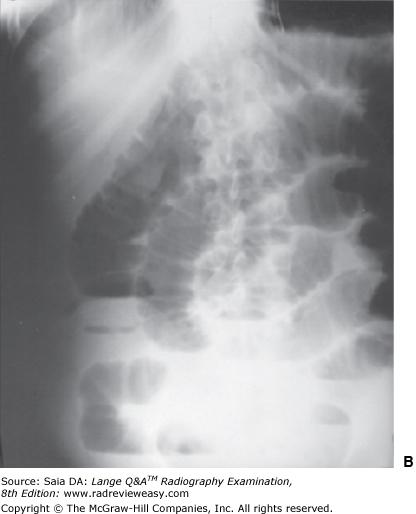

Which of the following statements is (are) true regarding the radiograph shown in Figure 6–16?

- The part is rotated.

- The patient is not shielded correctly.

- There is excessive receptor exposure.

A 1 only

B 2 only

C 1 and 2 only

D 1, 2, and 3

-The patient is well positioned; the spinous processes and sternum are seen clearly without superimposition. Adequate penetration and long-scale contrast are present without excessive receptor exposure. The patient had been shielded properly for the PA projection, but the shield was not moved to the correct location prior to the lateral exposure.